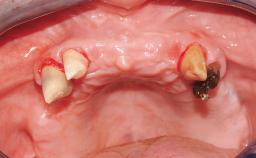

A 63-year-old male patient was referred for a consultation and treatment of partial edentulism in the maxilla. The patient presented with residual anterior teeth and declined a partial removable prosthesis. He reported that the maxillary posterior teeth had been extracted due to mobility and periodontal disease two months before the consultation. The patient’s chief complaint was that his residual maxillary teeth were mobile and that he was unable to chew. The patient’s desire was a stable and comfortable fixed maxillary rehabilitation. The patient was a light smoker (fewer than 10 cigarettes/ day), and his medical history was without significant findings. He was not on any regular medication at the time of consultation. The extraoral examination revealed a normal physiognomy with a correct distribution of the facial thirds. The patient presented a low lip line, and the transition line between teeth and soft tissues was not exposed during a forced smile.

Defining Characteristics Fully edentulous upper jaw to be rehabilitated with four or more implants

Bone Volume Horizontally and vertically sufficient